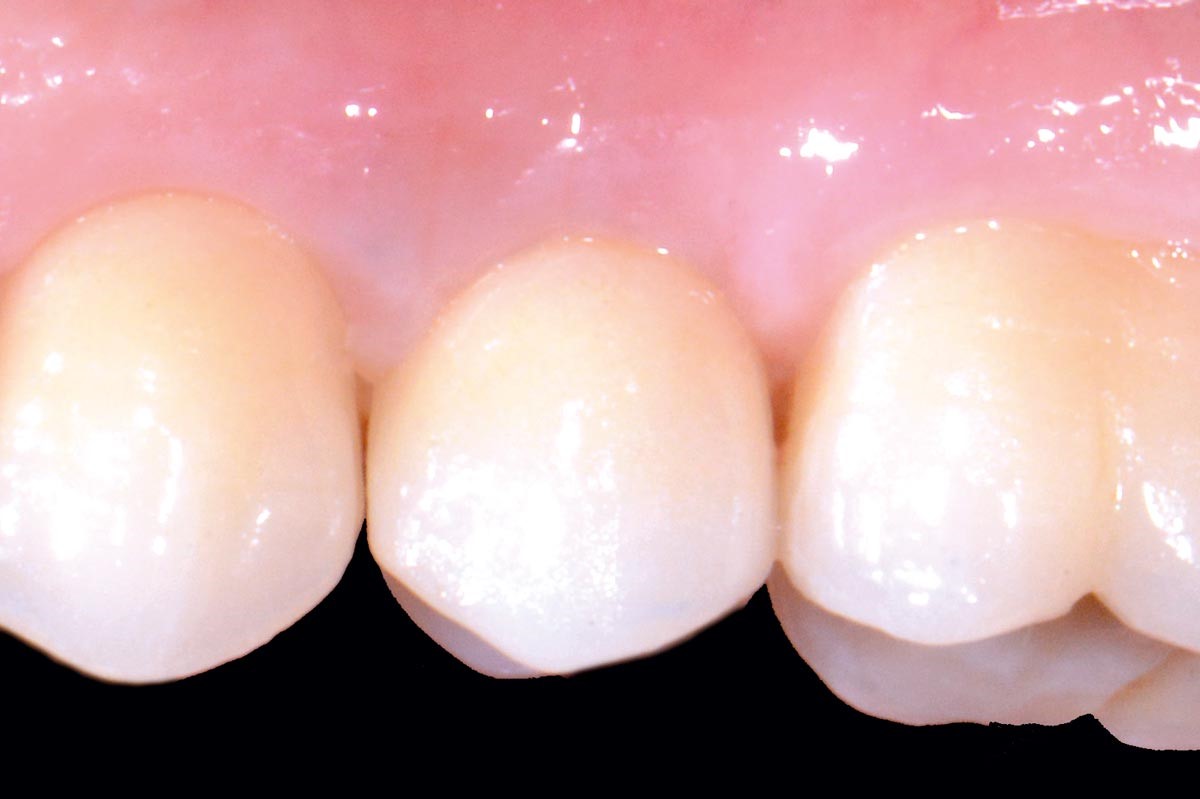

14/16 - Final prosthetic restoration with Zirconia crown at 1 year follow up (Prosthodontist: Dr. Elie Sawdayee)Full bone regeneration in extraction socket augmented with maxgraft® and Jason® membrane – Dr. C. Landsberg

15/16 - Final prosthetic restoration with Zirconia crown at 1 year follow up (Prosthodontist: Dr. Elie Sawdayee)Full bone regeneration in extraction socket augmented with maxgraft® and Jason® membrane – Dr. C. Landsberg